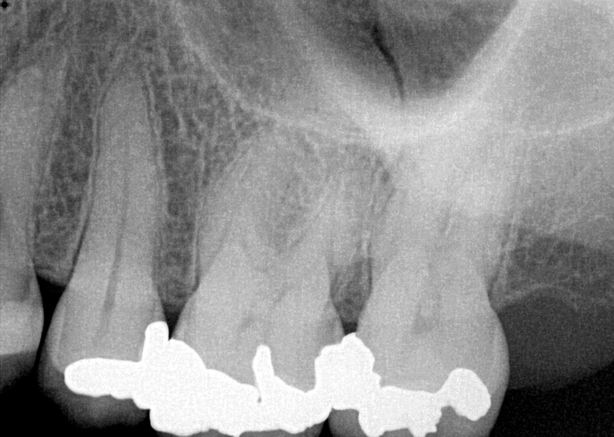

Fig 3. Preoperative maxillary left bicuspid.

Figure 3

The patient presented with temperature sensitivity and pain during mastication (Figure 3). Local anesthesia was delivered, and steps 1 through 4 were performed.